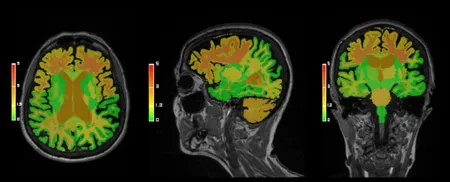

CTやMRIの脳血流画像から、脳血流パラメーターを自動計測、各種脳画像マップを作成して、診断に必要な情報を提供します。

MRI画像やCT画像から、脳容積や高信号領域の容積を自動計測して、診断治療に必要な情報を提供します。

脳に対するMR画像診断支援として転送された画像からAIアルゴリズムにより自動的に脳の形態解析を実行し、結果を出力。

頭部MRI画像から認知症リスク因子となる脳全体の萎縮度と白質病変量を定量評価するサービスです。

本サービスは、頭部MRIを用いて記憶に関わりの深い海馬の体積をAIにより計測するサービスです。